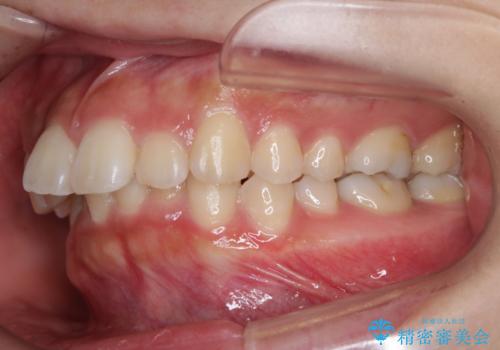

- 前歯のがたつきが気になるとご相談にいらした方です。当初は前歯の部分矯正をご希望されていましたが、全体的に整えることで審美的、機能的な歯並びとなりました。

当初は上顎前歯のみの部分矯正をご希望されていましたが、部分的に前歯のみを並べると出っ歯感がつよくなり、食事もしづらくなる可能性をお伝えしました。全顎的な矯正治療により、審美的、機能的な歯並びとなりました。